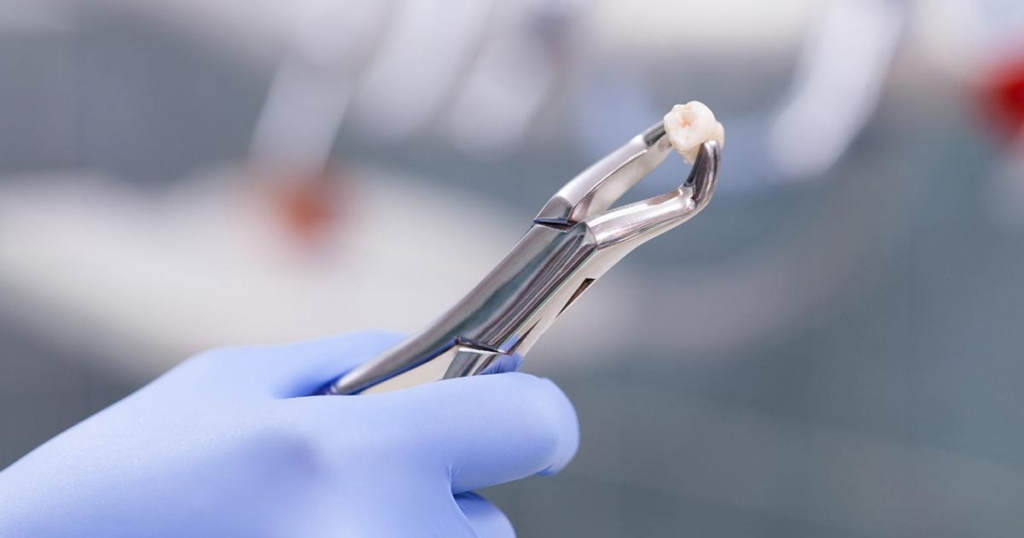

| Estrazione del 3° molare | 1500 – 3000 lei |